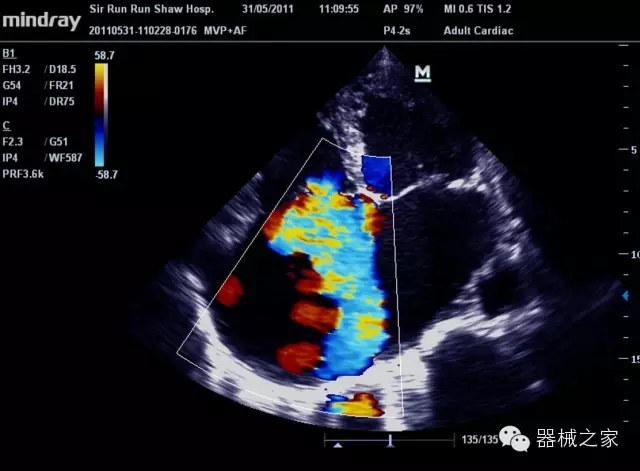

經(jīng)典產(chǎn)品:M7(星鉆)

臨床圖片賞析

產(chǎn)品特點

·裝載有采用Multi-Core多核處理的非嵌入式平臺,成像效率大大提高,并且能夠給用戶帶來高速、多任務(wù)并行信號處理體驗;

·優(yōu)秀的圖像效果、強大的功能體驗、豐富的探頭選擇、合理的便攜式設(shè)計,全中文顯示及病人管理界面,使得M7在任何場合、任何時候都能快速響應(yīng)更好的心血管、腹部、婦產(chǎn)、小器官等常規(guī)超聲檢查以及肌骨、神經(jīng)、顱腦、術(shù)中等新興領(lǐng)域的使用需求;

8倍波束并行處理系統(tǒng)

·在便攜式緊湊平臺上采用更多倍波束并行接收信號處理模式,無論二維還是彩色血流圖像狀態(tài)下,擁有更靈敏的回波頻移捕獲能力,大大提高時間分辨率,尤其使得心血管表現(xiàn)更為突出;

PSHI?寬帶頻移諧波技術(shù)

·在普通組織諧波的基礎(chǔ)上,通過精確控制的波束形成器,發(fā)射兩組具有相位偏差反向的信號,并采用并行信號處理,數(shù)字化合成并采樣回波信號,在高靈敏度的濾波器的處理過程中獲取更純凈的諧波信號,使圖像具有更加出眾的細節(jié)分辨率;

iClear®+iBeam?

·智能化按線復(fù)合多角度獲取聲束的原始信號,配合智能化的斑點噪聲識別及控制處理技術(shù),整體提高組織結(jié)構(gòu)細節(jié)分辨率,任何時候都能快速響應(yīng),更好的滿足心血管的使用需求;

支持全新3T工藝探頭群

·包括探頭材料、結(jié)構(gòu)設(shè)計、加工工藝三方面的革新技術(shù)給圖像帶來品質(zhì)的飛躍;